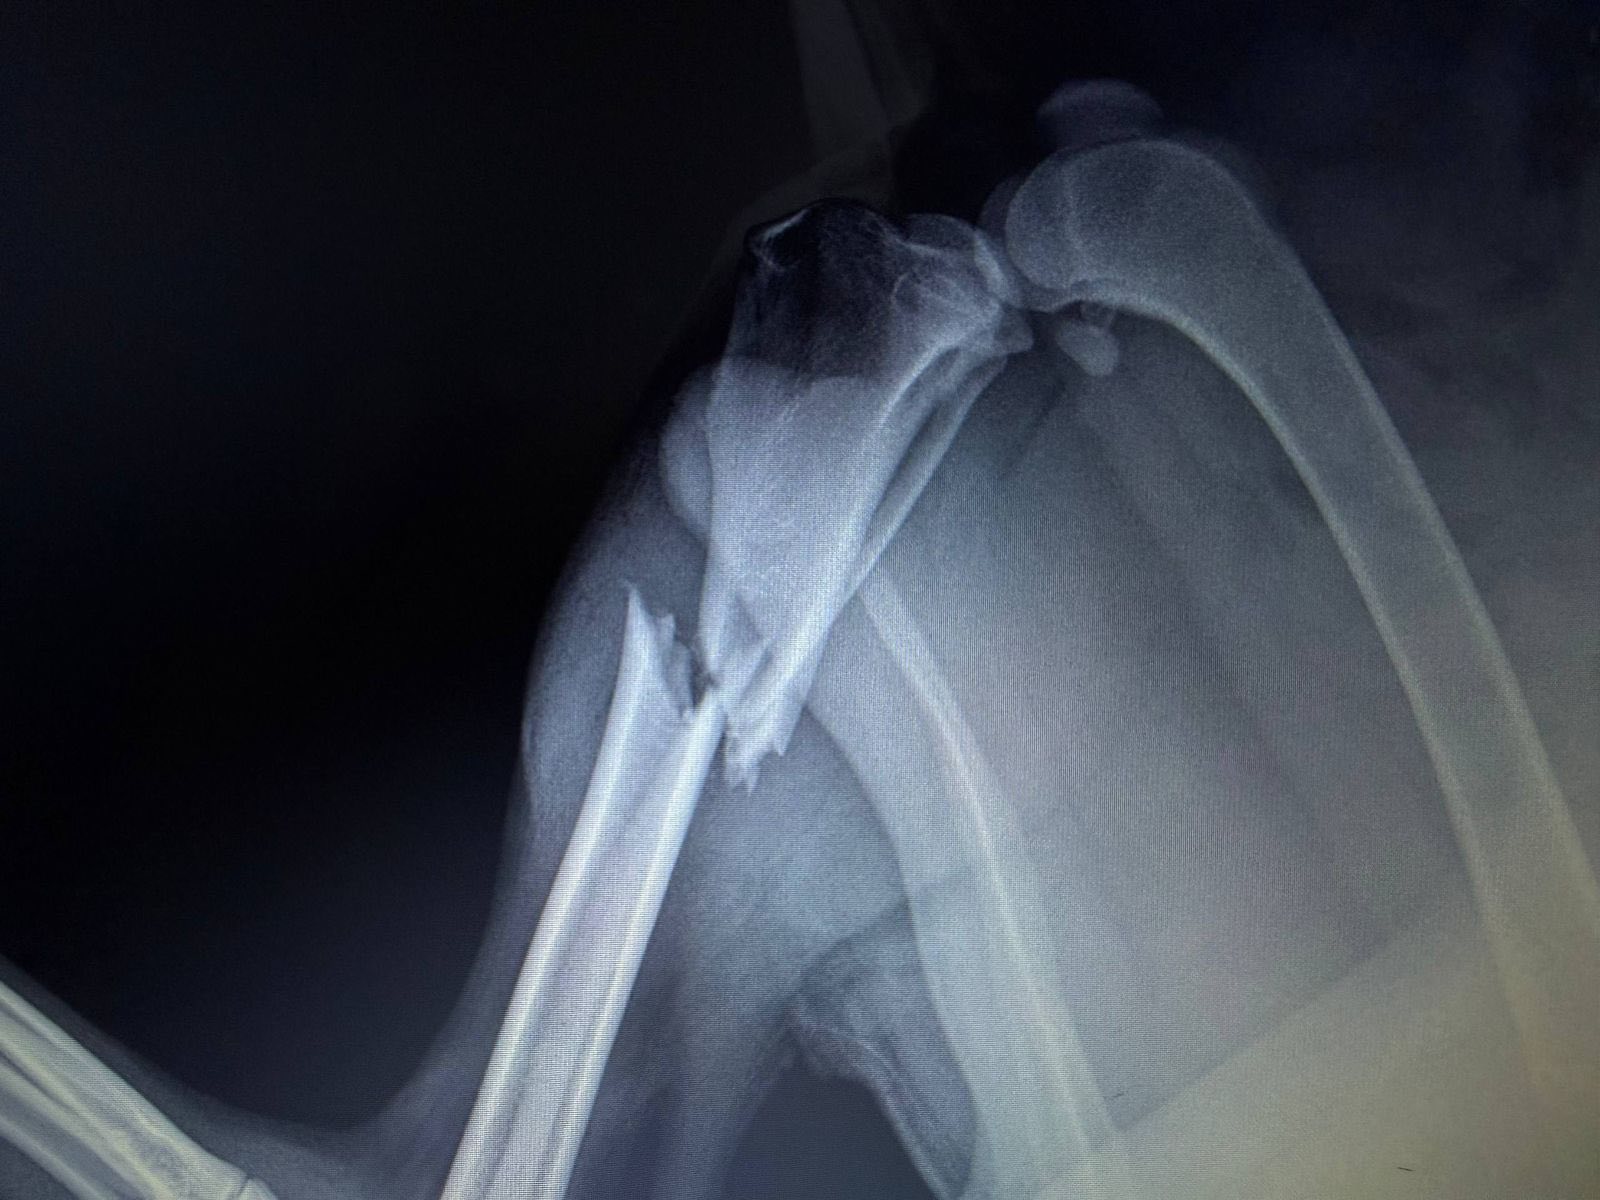

После осмотра врачи установили перелом голени задней лапы.

Ветеринары провели срочную операцию, которая прошла успешно.